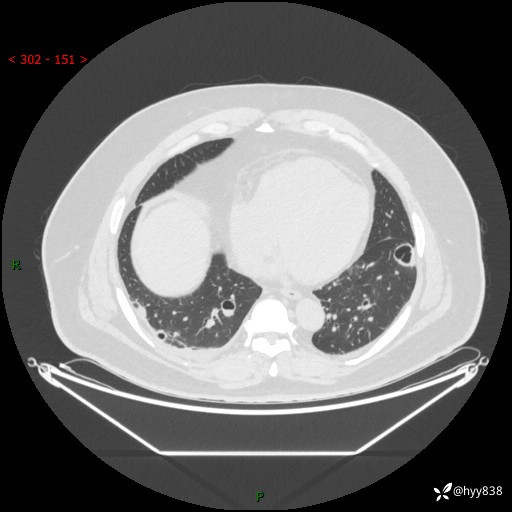

性别:男

年龄:48岁

简要病史:发热来诊(门诊病人)

胸部CT平扫